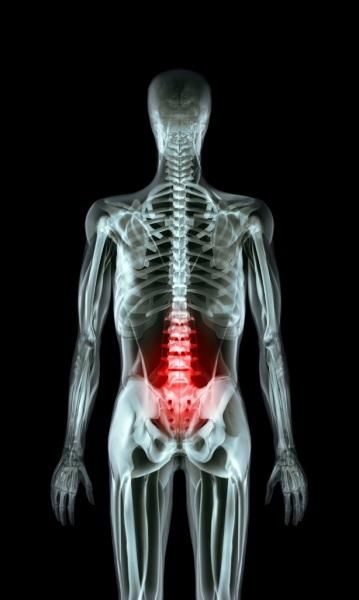

Le parti del corpo che non usiamo più!

L’evoluzione umana è un evento fondamentale che ha permesso alla nostra specie di evolversi sviluppando caratteri o parti del corpo completamente nuovi nel corso del tempo. I nuovi adattamenti sono molto importanti per sopravvivere nell’ambiente che cambia nel tempo. Infatti, le modifiche ambientali fanno prendere provvedimenti al corpo.

Tuttavia, come ha descritto la prestigiosa rivista scientifica Focus, ci sono delle parti del corpo che non usiamo più. Quali sono, allora, le parti del corpo “inutili”?